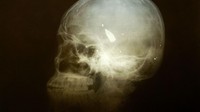

Sebuah peluru terlihat bersanga di dalam tengkorak di Baghdad, Irak. Diketahui, peluru tersebut merupakan peluru nyasar imbas konflik pada 22 April 2003 lalu.